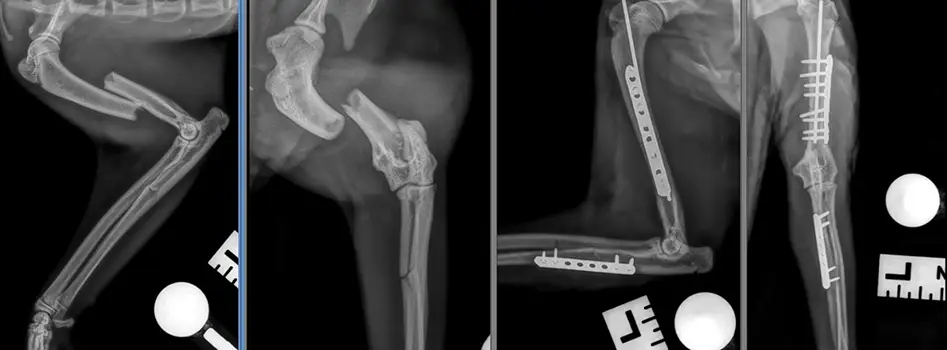

“Radiographs showed he had several very serious fractures, so we stabilised him over night before carrying out the surgery the following day.

“We reduced and stabilised one of his fractures by putting a pin down the bone and a plate and screws to hold the fragments in place, before using a plate and screws to prevent another fracture from becoming displaced.